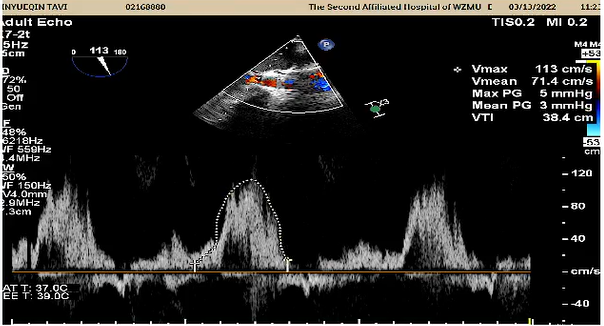

7.超声显示最大流速降至1.13m/s,平均跨瓣压差约3mmHg;

8.撤出猪尾导管,造影显示无瓣周漏,手术圆满成功。